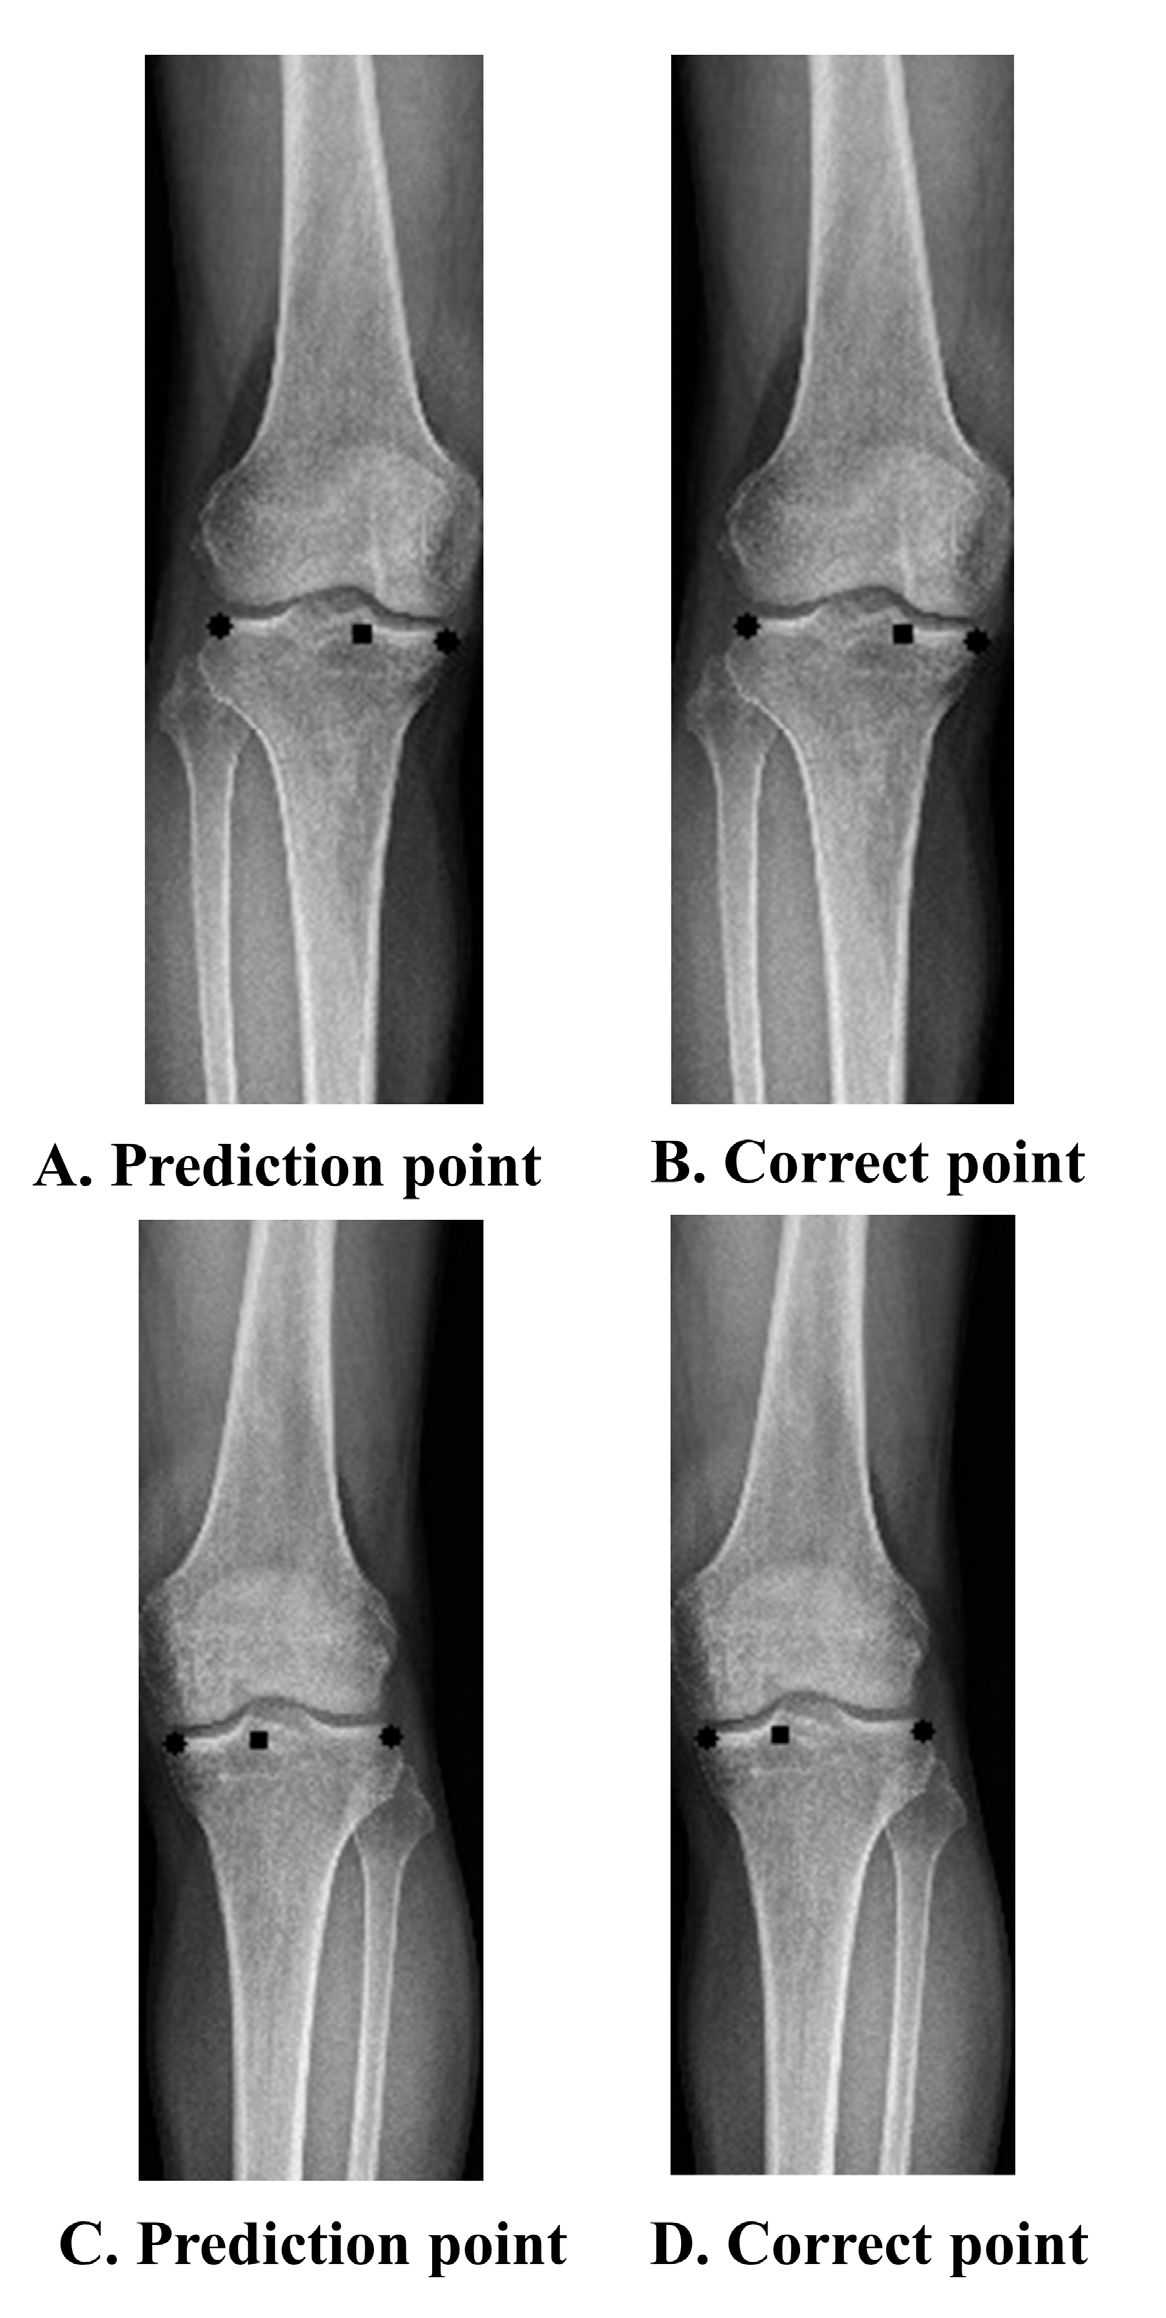

The baseline characteristics of the patients and the distribution of the labels in the training, validation, and test sets are summarized in Table 1. Age, sex, BMI, and WBL ratio were not significantly different between the datasets. The performance was improved through simple labeling that marked both ends of the tibia and the starting and exit points of the WBL line. Four points indicated the best performance among the trials. A comparison of the WBL mean accuracy at 4 and 27 points is shown in Figure 2. As the threshold of the WBL error percentage value increased, the accuracy of taking four points approached 0.6, whereas when 27 points were taken, a steady state was reached with an accuracy not exceeding 0.1. These results were also similarly obtained in the pixel unit, and as the threshold increased, the accuracy when taking four points was close to 0.8 in 6 pixels, while that achieved when taking 27 points was approximately 0.2 in 6 pixels. A representative example of a patient’s difference between the predicted and the correct points on an X-ray image is shown in Figure 3. The differences between the actual measured WBL ratio and the WBL ratio predicted by the CNN in this patient were 0.03 in the right knee and 0.05 in the left knee.

Figure 3. Prediction and correct point. (AD) Prediction point vs. correct point. (A) Prediction point in Rt knee, (B) correct point in Rt knee, (C) prediction point in Lt knee, (D) correct point in Lt knee. Prediction point: point predicted by the deep learning algorithm. Correct point: labeled point.